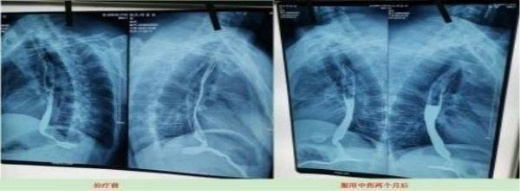

案例6、食道癌两个月清零

患者:刘喜良 男 46岁 食道中段癌

2023年10月9日CT影响报告诊断查出食管壁增厚,管腔狭窄,食管癌。找到陈海林老师使用中医药两个月治疗后CT显示食管各段顺利通过,食管恶性肿瘤治疗后改变。

Patient: Liu Xiliang, male, 46-year-old middle-esophageal cancer On 9 October 2023, CT affected the diagnosis of food tube wall thickening, lumen stenosis, and esophageal cancer. After finding Chen Hailin for two months, CT treatment showed the smooth passage of all section of the esophagus, and the esophagus of malignant tumor changed after treatment.

上图是服用两个月中药的前后对比图

Above is a comparison of before and after taking traditional Chinese medicine for two months

上图是服用两个月中药后检查报告对比图

The figure above is a comparison diagram of the examination report after taking TCM for two months